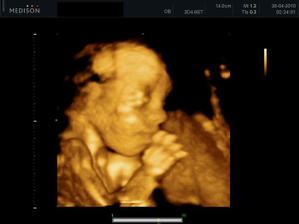

27.04. - (24+5) video, tak z videa nakonec sešlo. Dohodli jsme se s panem doktorem, že se mu ozvu, tak za 14 dní, až Karolínka ještě povyroste. Teď má v bříšku ještě moc místa a nebylo by to úplně ono. Tak jsme alespoň dostali několik foteček a dva doktoři nám potvrdili, že jde skutečně o holčičku.

11.05. - (26+5) dnes jedeme na video

video se povedlo, máme asi 6 cca 5 - 10ti vteřinových videíí.Bylo to super. Karolínka se zase mlela jako drak. Je taková živoučká 😀